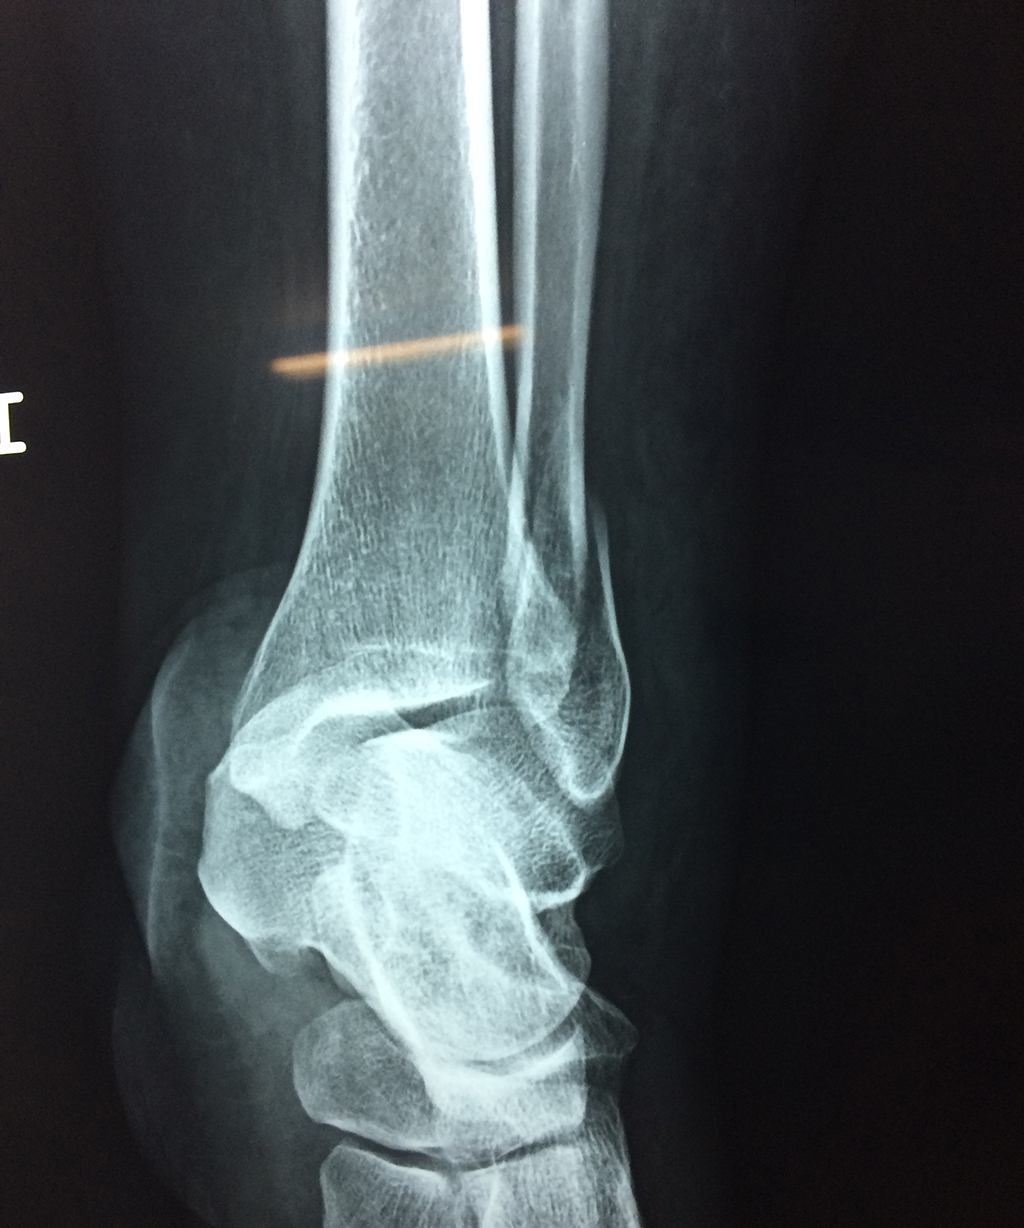

Una fractura de tobillo es la rotura de uno o más de los huesos del tobillo. Estas fracturas pueden ser:

- Los extremos de los huesos están desalineados entre sí (desplazados).

- La fractura se extiende hasta la articulación del tobillo (fractura intra-articular).

- Los tendones o ligamentos (tejidos que sujetan los músculos y los huesos entre sí) están rotos.